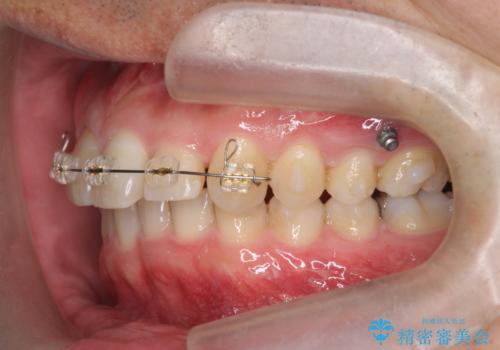

2級ディープバイト 遠心移動を伴うマウスピース矯正

・深い噛み合わせ(ディープバイト) ・2級性の咬合関係(上顎前突)・前歯のがたつき

以上のような歯並びの問題をマウスピース矯正インビザライン・カリエール・マイクロインプラント・部分ワイヤー矯正

を用いて改善していきます。

深い噛み合わせと上顎前突の状態を治すのに時間がかかりましたが、治療後は理想的で安定した咬合関係となりました。